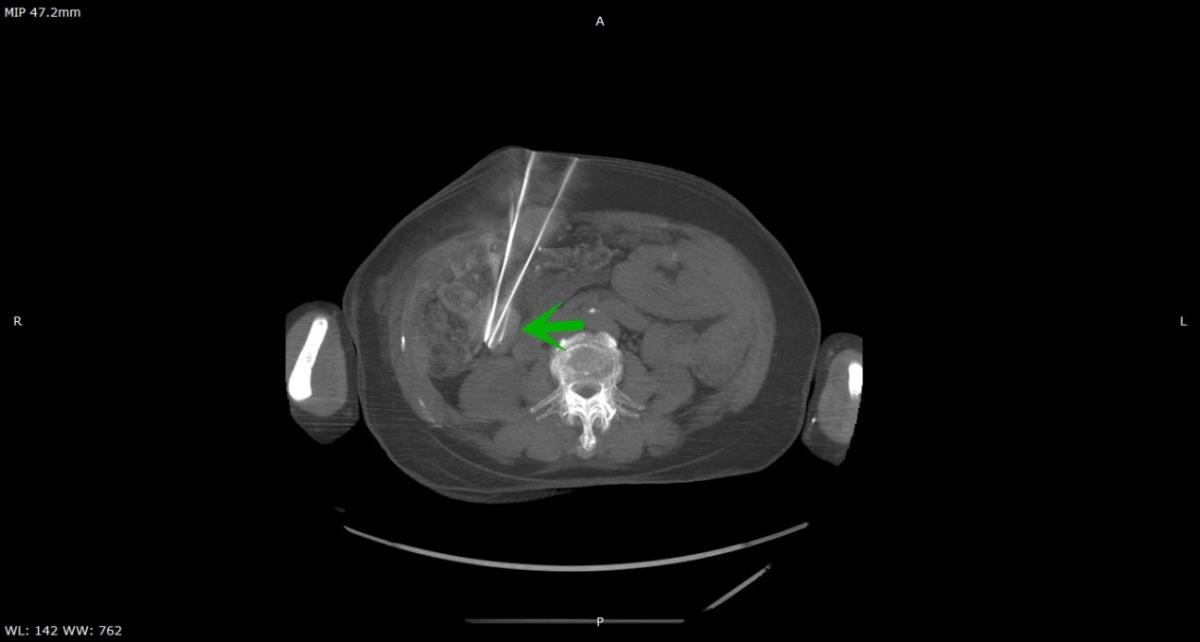

病例二:患者范某,女,82岁,卵巢癌腹部多发转移瘤行粒子植入手术。转移瘤大小约3cmx4cmx3.5cm,拟分布3根穿刺针,植入12颗粒子。转移瘤贴近肾脏边缘,位于肾动脉旁,穿刺位置深度达18cm,进针路径中需要避开腹部肠管,手术风险非常高。术中通过导航机器人计划系统一次布置3针,均采用一步进针方式完成,通过机器人验证系统可以看到进针全部到达靶区,术后验证与计划处置完全一致,穿刺位置非常理想,行粒子植入手术。术中CT扫描3次,计划处置时间13min,术后未发生并发症。

穿刺结果与计划完全一致